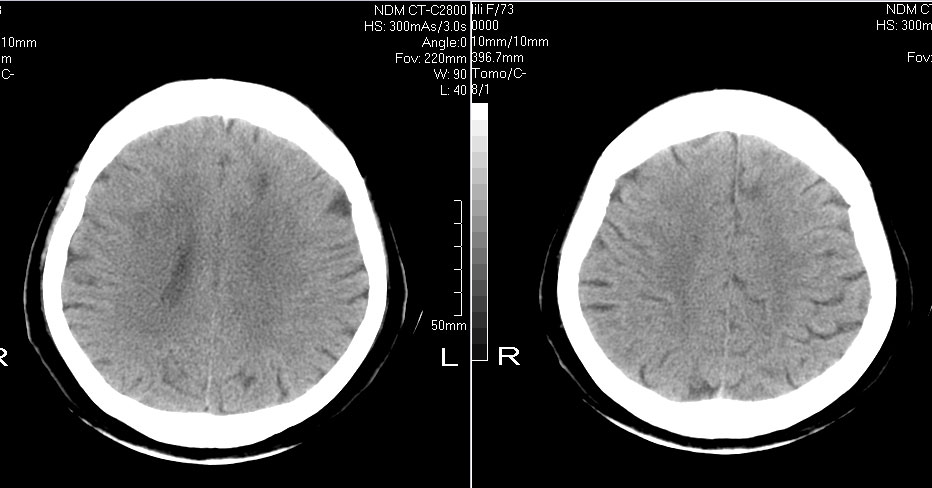

标题: CT10819:女,72,有高血压病史,突然寡言少语3日. [打印本页]

女,72,有高血压病史,突然寡言少语3日.

双侧基底节、胼胝体膝部多发腔隙性脑梗塞。